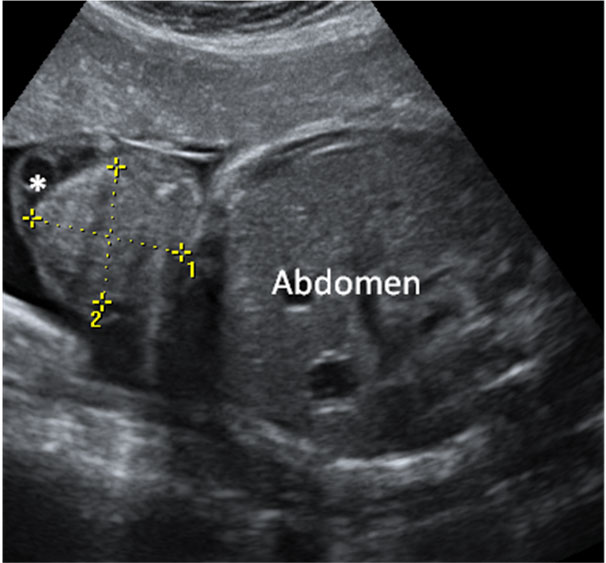

Las ecografías en 2D y en 3D en la semana 20 de embarazo permite diagnosticar algunas malformaciones congénitas fetales, como el labio leporino, que se visualiza en estas imágenes.